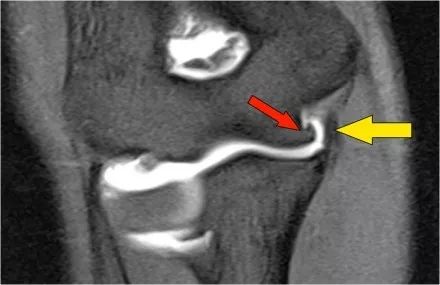

下面是一名18岁的棒球投手,内侧肘部疼痛。看到局部撕裂产生'T标志'。